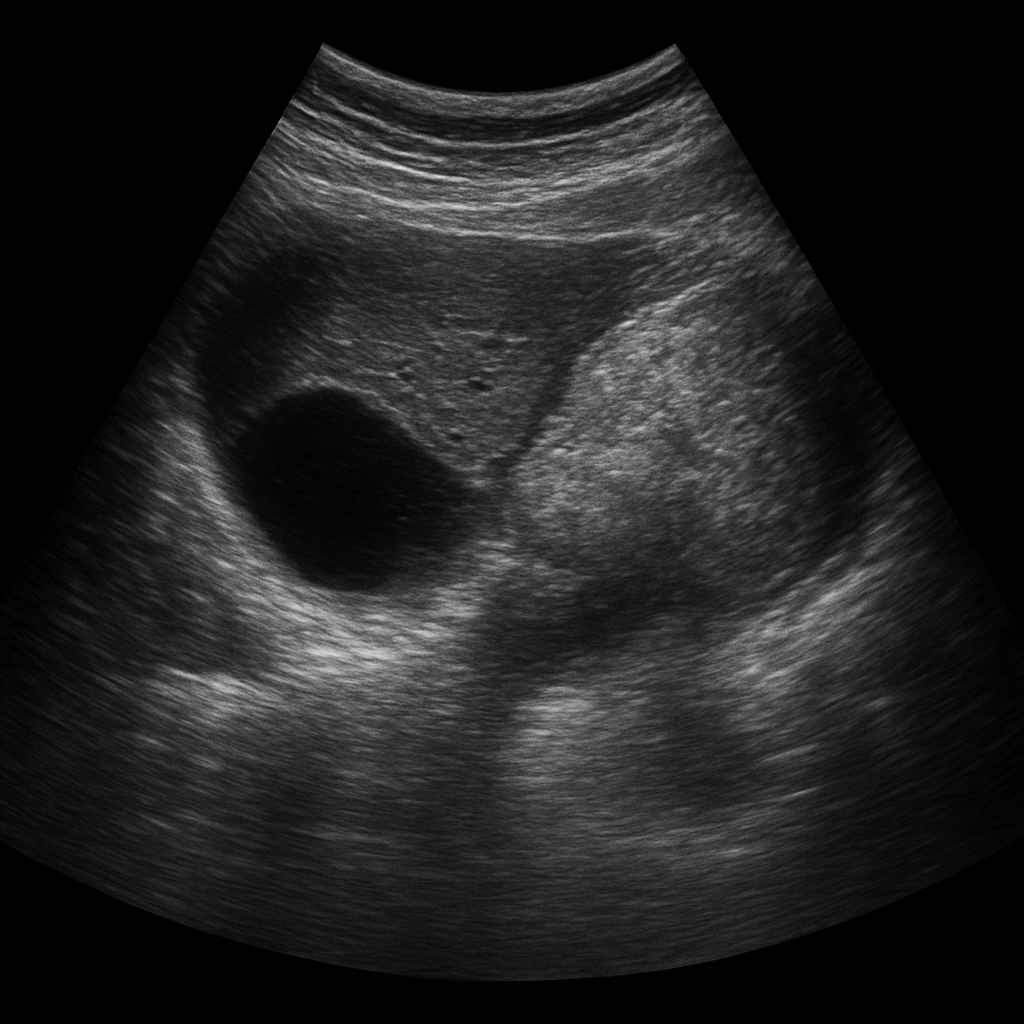

L’ Échographie abdominale est un examen d’imagerie médicale couramment utilisé pour explorer l’intérieur de l’abdomen de manière non invasive. Grâce aux ultrasons, elle permet de visualiser en temps réel certains organes abdominaux, sans douleur ni exposition aux rayons X. C’est l’un des examens les plus prescrits en médecine générale et spécialisée.

L’échographie abdominale repose sur l’émission d’ondes ultrasonores à haute fréquence à travers une sonde, appliquée sur la peau. Ces ondes se propagent à travers les tissus et sont réfléchies différemment selon la nature des structures qu’elles rencontrent (liquide, tissu dense, gaz, os). Le signal de retour est interprété par un logiciel informatique qui crée des images en temps réel.

Le radiologue, ou le médecin échographiste, peut ainsi observer l’aspect des organes, rechercher des anomalies morphologiques, mesurer des structures et, dans certains cas, guider des gestes diagnostiques ou thérapeutiques.

1. Le foie

L’échographie hépatique permet d’évaluer la taille, la structure (stéatose, nodules, tumeurs), la texture (cirrhose), et la vascularisation du foie. Elle est utile dans le suivi des hépatopathies chroniques.

2. La vésicule biliaire

On y recherche des calculs biliaires (lithiases), une inflammation de la paroi (cholécystite), ou des polypes. Cet organe est facilement accessible par échographie, notamment après un jeûne.

3. Les reins et voies urinaires hautes

Les reins peuvent être explorés à la recherche de calculs rénaux, de kystes, de tumeurs, ou encore d’une dilatation des cavités rénales (hydronéphrose). On peut aussi y dépister une malformation congénitale ou une infection (comme une pyélonéphrite), bien que le diagnostic repose avant tout sur la clinique et le scanner.